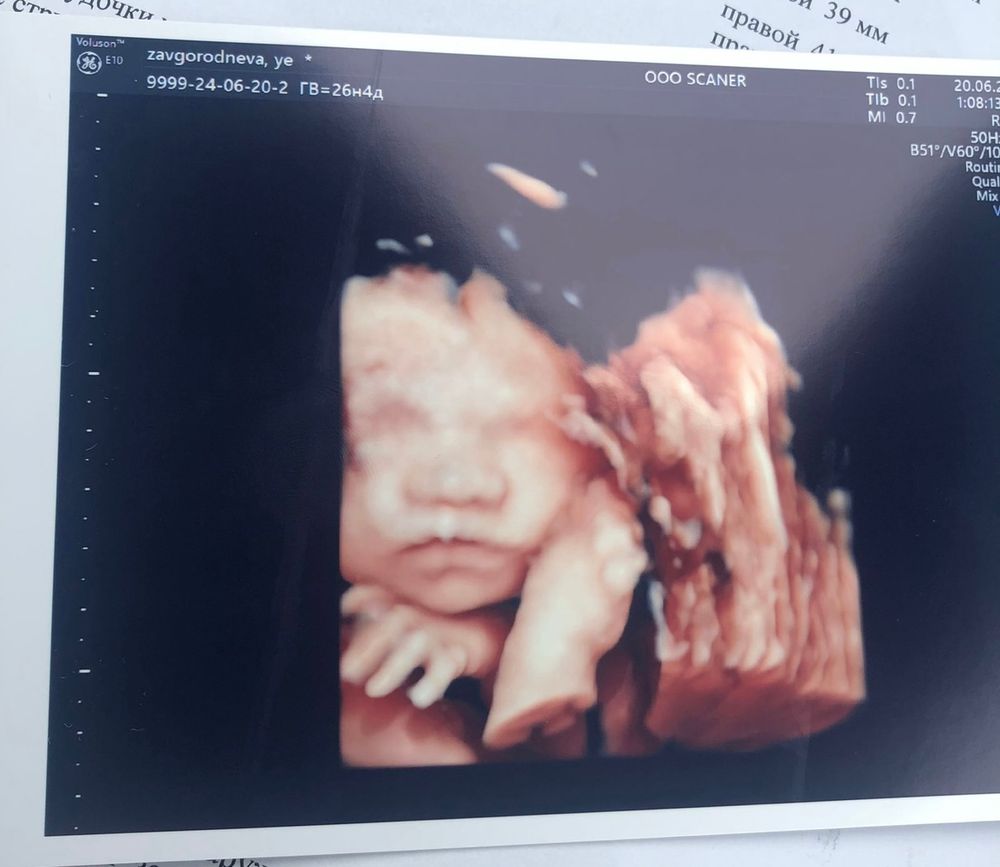

На мой взгляд не сильно 3д похоже)ну судите сами.после родов фото и сейчас .Изображение Изображение Изображение

Ага,но родилась вроде бы не с таким большим и отечным носом 😹🗿 Изображение Изображение Изображение

На узи в 16 Нед был большой носик по сравнению с лицом , в остальные сроки был можно сказать как и при рождении Изображение Изображение Изображение